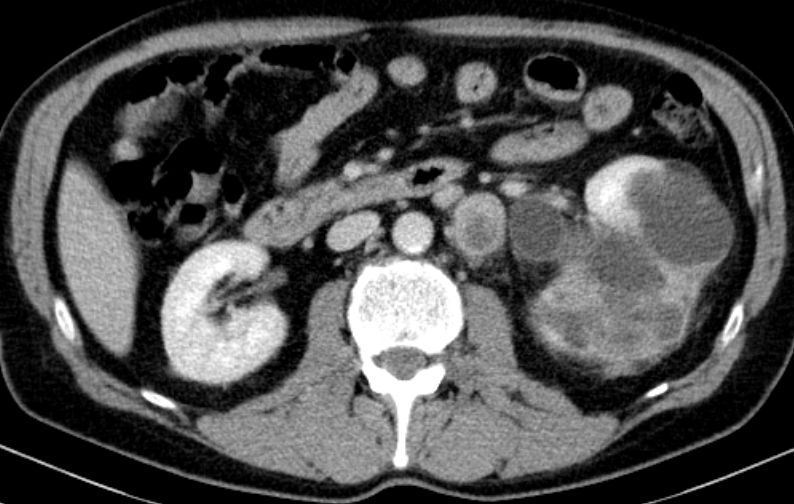

Urothelkarzinom der Niere 81-jährige Frau mit einem großen, die linke Niere einnehmendem Tumor. Histologie: Urothelkarzinom.

Die linke Nierenarterie ist von LK-Metastasen eingeschlossen.